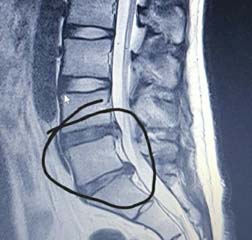

이번 포스팅에서 허리디스크에 좋은 운동 10가지에 대하여서 알아볼꺼에요. 허리는 우리 몸무게의 약 60%를 지탱하고 있습니다. 상당히 귀중한 육체 부위에요.

사무실이나 집에서 컴퓨터나 노트북을 하는 직장인들이 많다고 해서지면서 허리디스크 통증을 호소하는

분들이 불어나고 있다고 합니다.

허리디스크에 대해 아직 살펴보지 못하셨다면 허리디스크가 어느 부위를 말하는지 확인하시고 시기에 맞추어 운동하여 주십시요.

서울대 재활의학과 교수님이 쓴 책의 내용인데 1주일에 20km 이상을 달리는 사람과 운동은 하지 않는 사람들을 비교해 봤을 때, MRI 영상에서 달리기를 꾸준히 하는 사람들이 허리디스크가 두꺼웠고 그 속의 수분 함유하고 있는 분량이 높았다는 내용이 있었습니다.